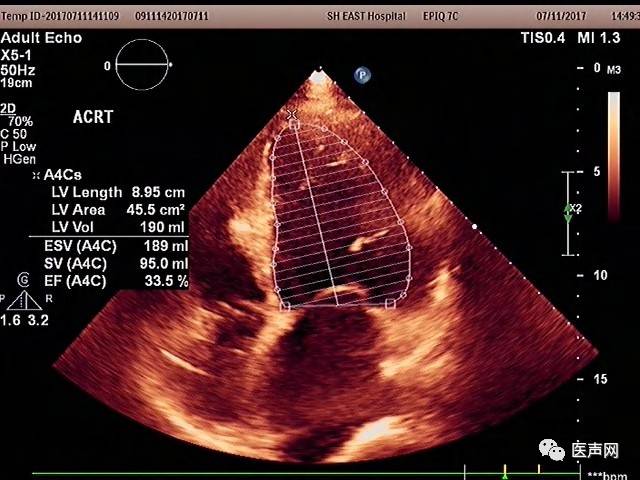

术后1周患者心力衰竭症状明显改善,LVEF<33%

术后心电图QRS时限缩窄到 112 ms,术后心电图(图2)

术后彩超优化

术后彩超: